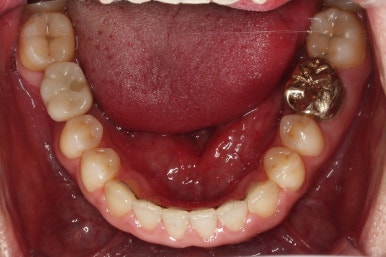

교정치료도 종료 되었고 연산동임플란트 잘 완성이 되었어요.

총 14개월이 걸린 치료였는데 비교적 짧은 기간 내에 틈새도 모으고, 임플란트 및 충치치료도 다 완료를 할 수 있었습니다.

전후 사진을 비교해 볼게요.

비교적 짧은 시간 안에 환자분이 만족하는 치료를 할 수 있었어요.